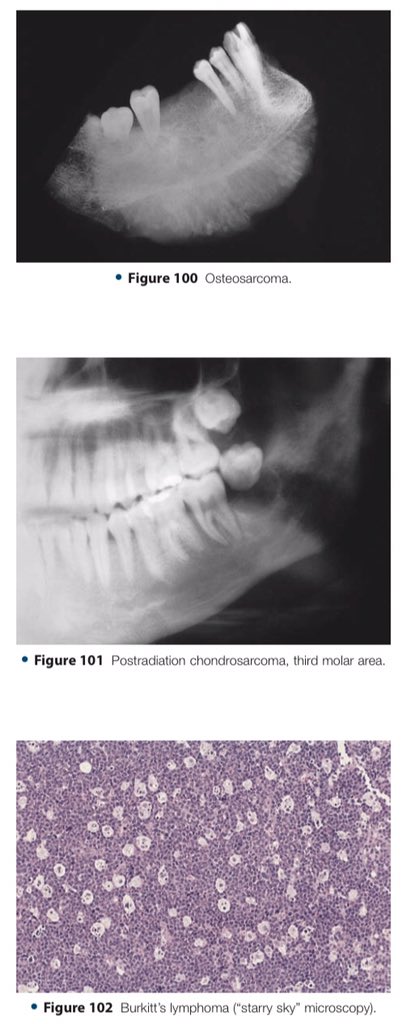

🔍| Differential Diagnosis Approach to Jaw Lesions. #aboutDent